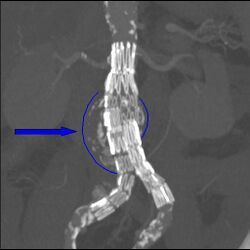

Abdominal aortic endoprosthesis, CT scan, original aneurysm marked in blue

Endovascular repair first became practical in the 1990s and although it is now an established alternative to open repair, its role is yet to be clearly defined. It is generally indicated in older, high-risk patients or patients unfit for open repair. However, endovascular repair is feasible for only a portion of AAAs, depending on the morphology of the aneurysm. The main advantages over open repair are that there is less peri-operative mortality, less time in intensive care, less time in hospital overall and earlier return to normal activity. Disadvantages of endovascular repair include a requirement for more frequent ongoing hospital reviews and a higher chance of further required procedures. According to the latest studies, the EVAR procedure does not offer any benefit for overall survival or health-related quality of life compared to open surgery, although aneurysm-related mortality is lower.[55][56][57][58] In patients unfit for open repair, EVAR plus conservative management was associated with no benefit, more complications, subsequent procedures and higher costs compared to conservative management alone.[59] Endovascular treatment for paraanastomotic aneurysms after aortobiiliac reconstruction is also a possibility.[60] A 2017 Cochrane review found tentative evidence of no difference in outcomes between endovascular and open repair of ruptured AAA in the first month.[61]